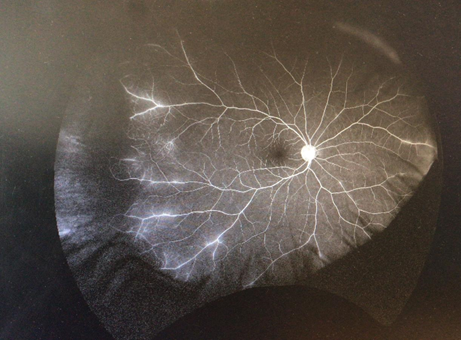

Une patiente de 26 ans se déplace pour une myopie : Aucune plainte visuelle Fond d'oeil non dilaté L'ophtalmologue diagnostique un décollement de la rétine inférieure à progression lente, qui nécessite une intervention d'urgence.